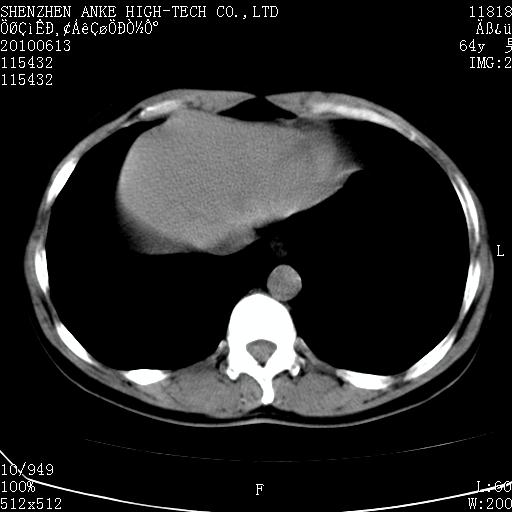

以下是引用beifangren在2010-7-26 22:05:00的发言:[br]左肾中极圆形占位,肾盏肾盂受压移位,建议增强。结合肺部结节。肝低密度灶,多为肾癌并肺部、肝转移。